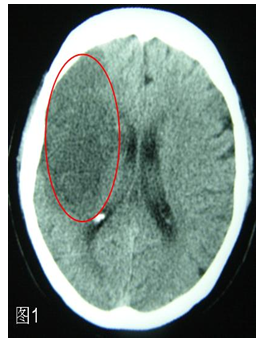

(1)首先应该做头颅CT

在某些地方也把头颅CT更形象地称作“脑扫描”。CT可以在最快的时间内了解,因为脑动脉堵塞而发生了脑梗死还是脑动脉破裂而出现了脑出血。脑梗死时头颅CT发现在脑组织出现了片状的黑色图像(图1),脑出血时可见在脑组织中出现了白色的团块(图2),一目了然。所以,得了脑卒中,第一要做的检查就是头颅CT。